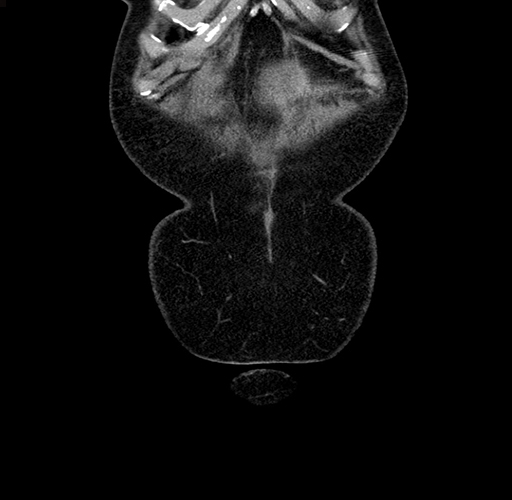

Pre-Chemo: Coronal Venous